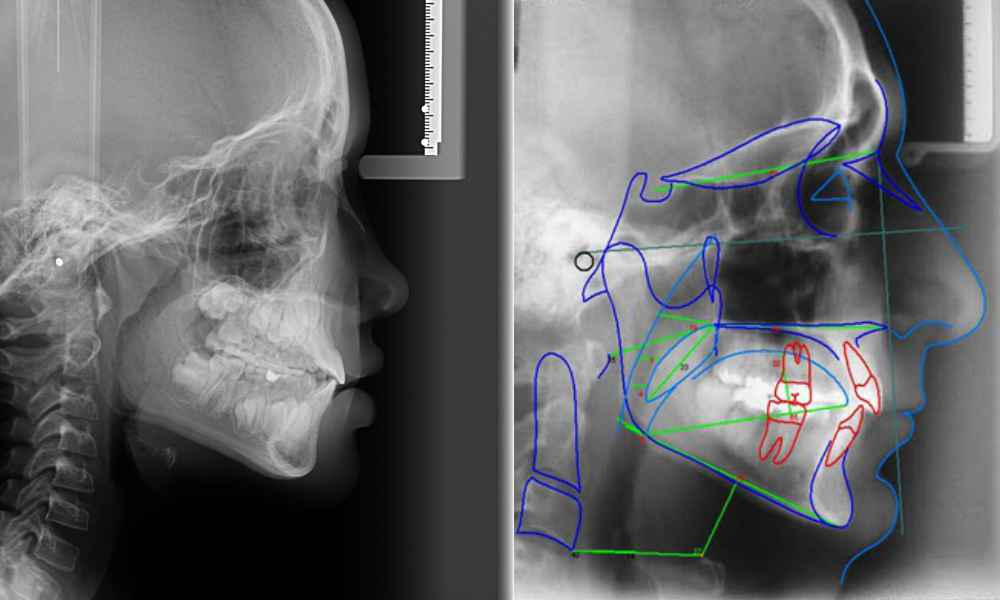

DIAGNÓSTICO 2D

La ortodoncia, históricamente ha usado las radiografías tradicionales como examen complementario de los pacientes. Este método se sigue usando, principalmente en los niños, aportando mucha información relevante.